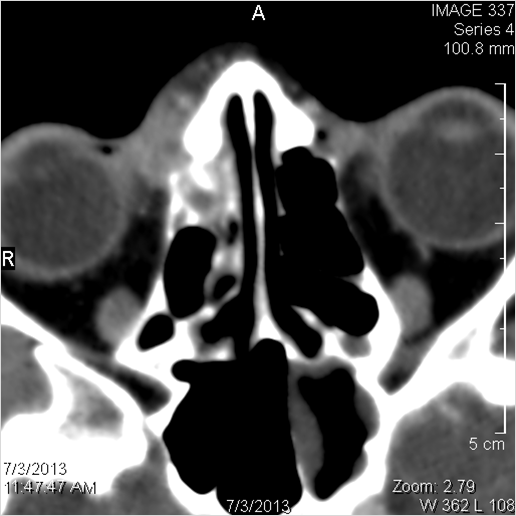

Nasal Cavity and Nasolacrimal Drainage System

There is mucoperiosteal thickening in the nasal cavity.

There is mucosal thickening of the posterior lateral walls of the nasal cavity, cribriform plate or the face of the sphenoid bone.

There is infiltration of soft tissues or bone erosion along the nasolacrimal fossa or canal.